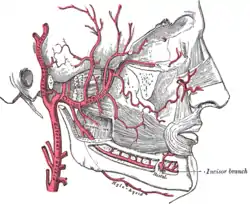

Plan of branches of internal maxillary artery. (Label "Deep auric." visible at upper left.) | |

Plan of branches of internal maxillary artery. (Deep auricular visible but not labeled.) | |

The deep auricular artery is a branch of the maxillary artery. The deep auricular artery pierces the external acoustic meatus. It provides arterial supply to the skin of the external acoustic meatus, and contributes arterial supply to the tympanic membrane, and (via a branch) the temporomandibular joint.[1]

It ascends[2] in the substance of the parotid gland, behind the temporomandibular articulation, and pierces the cartilaginous or bony wall of the external acoustic meatus[1] to course between the cartilage and bone.[2]

It supplies its cuticular lining and the outer surface of the tympanic membrane.

It gives a branch to the temporomandibular joint.[1]